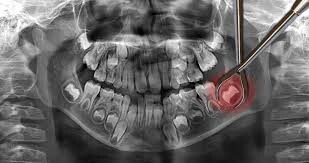

Impacted wisdom teeth hardly ever erupt

Not all wisdom teeth make it out of the gums. Some get impacted, meaning they are trapped in the jawbone or blocked by other teeth. This often happens when the wisdom teeth come in at an awkward angle. Impacted wisdom teeth can cause severe pain and will need to be removed through a surgical procedure.

Wisdom teeth extraction is not as painful as you thought

Many people may have mentioned that the process of extracting wisdom teeth is painful and debilitating. That is not always so if you undergo the procedure with a professional and experienced dentist. The dental expert will ensure maximum comfort during the procedure by administering anesthesia and other forms of sedation dentistry.